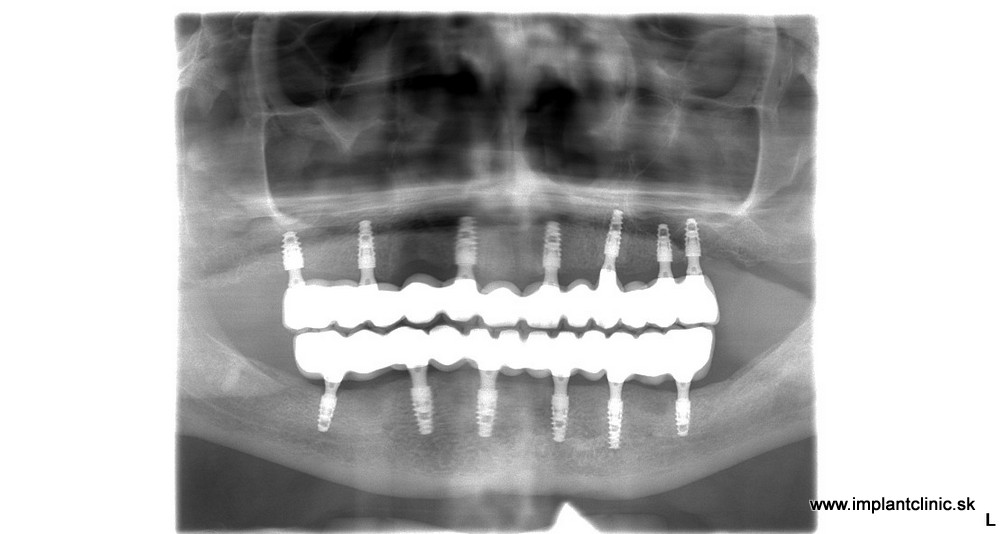

Michal sa objednal na konzultáciu v Implantclinic. Náš hlavný implantológ MUDr. Salka navrhol komplexnú rekonštrukciu chrupu hornej čeľusti a sánky. Konkrétne sa jednalo o zavedenie 7 zubných implantátov v hornej čeľusti a 6 zubných implantátov v sánke.

RTG snímka pred a po ošetrení: